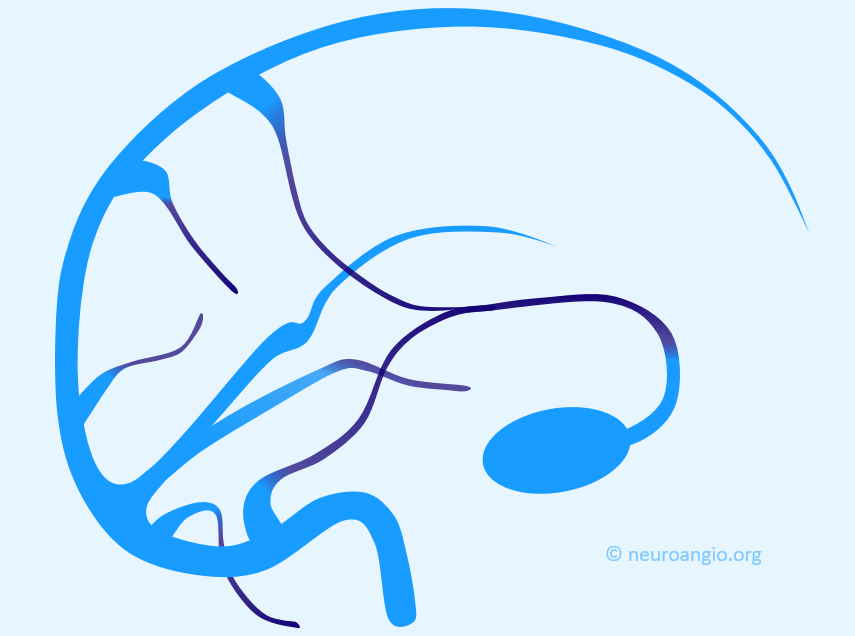

Some sinuses are present less commonly than others: the more uncommon ones are labeled in white. The superior and inferior sagittal sinuses are not shown to full extent for clarity. Note how the sphenoparietal sinus runs along the edge of the lesser sphenoid wing, and superior petrosal sinus follows the petrous ridge. Most people have quite asymmetric sinuses.